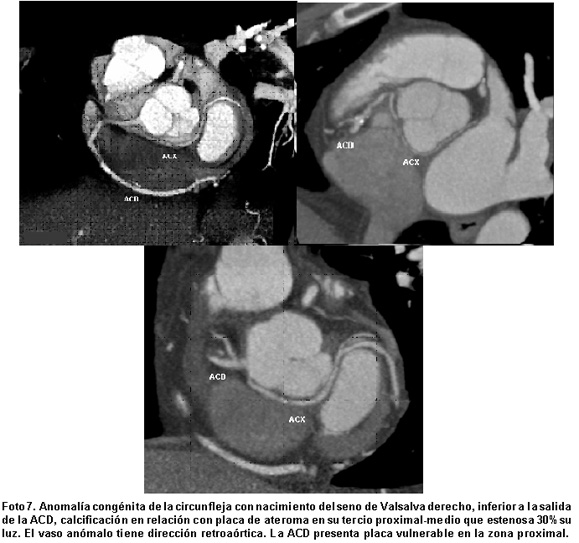

Las anomalías anatómicas más comunes en este estudio fueron la duplicación o triplicación de vasos coronarios con una frecuencia de 23% (Fotos 3 y 4) y ausencia de tronco izquierdo (15%), que no tienen interés clínico. De las anomalías con importancia clínica más frecuentes fueron la ACD con origen en el seno de Valsalva izquierdo y trayecto interarterial (15% Fotos 5 y 6), discurriendo entre la aorta y el tronco de la arteria pulmonar, patrón que se puede asociar con alto riesgo de isquemia inducida por ejercicio y muerte cardíaca súbita6. Otras anomalías son el origen aberrante de la ACX desde el seno de Valsalva derecho con o sin trayecto interarterial (15% casos. Foto 7) y el puente intramiocárdico (11%. Foto 8).

Cuando hay variaciones anatómicas en el origen de las arterias coronarias, resulta más fácil demostrar su recorrido mediante tomografía multidetector, porque esta técnica es capaz de demostrar con claridad la relación de la arteria anómala y otras estructuras adyacentes como el tronco pulmonar y la aorta, datos que son importantes, pues el recorrido puede ser posterior a la aorta (retroaórtico), entre la aorta ascendente y el tronco pulmonar/tracto de salida del ventrículo derecho (interarterial)11, o anterior al tronco pulmonar, teniendo un gran significado clínico el trayecto interarterial ya que se puede asociar con alto riesgo de muerte cardíaca súbita (Foto 9).